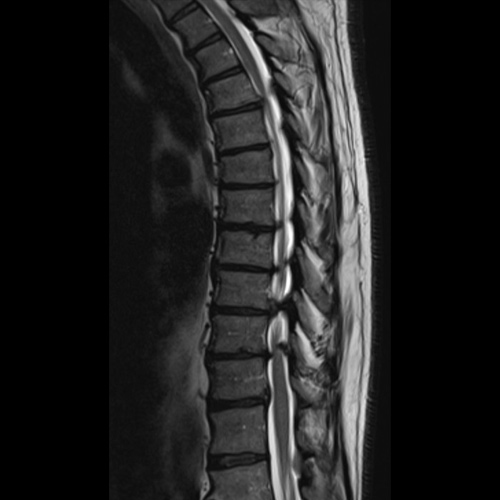

Spinal stenosis (Lumbar) Spinal stenosis (Cervical) Spinal stenosis (Thoracic) Lumbar Disc Herniation Spondylolisthesis Cervical Foraminal Stenosis Vertebroplasty Lumbar Fusion Anterior Cervical Fusion (ACDF) Posterior Cervical Fusion Thoracic Fusion Revision Lumbar Fusion Surgery Facet Joint Cyst Spinal Tumour Minimally Invasive Lumbar Fusion (XLIF) Minimally Invasive Lumbar Fusion (ALIF) Lumbar Fusion (TLIF) Thoraco-lumbar Fusion Lumbar Corpectomy Complex Lumbar Spine Surgery (Spino-pelvic fixation) Complex Cervical Spine Surgery Complex Thoracic Spine Surgery Occipito-cervical Fusion Minimally invasive surgery for thoracic disc herniation Other Related Topics